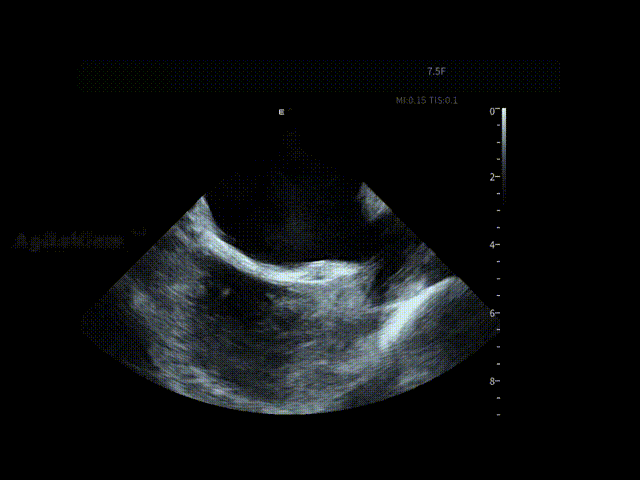

在全球最细7.5Fr ICE的持续影像引导下,手术路径清晰。随后,邹操教授在ICE下进行了房间隔穿刺,可见明显tenting现象。

房间隔穿刺